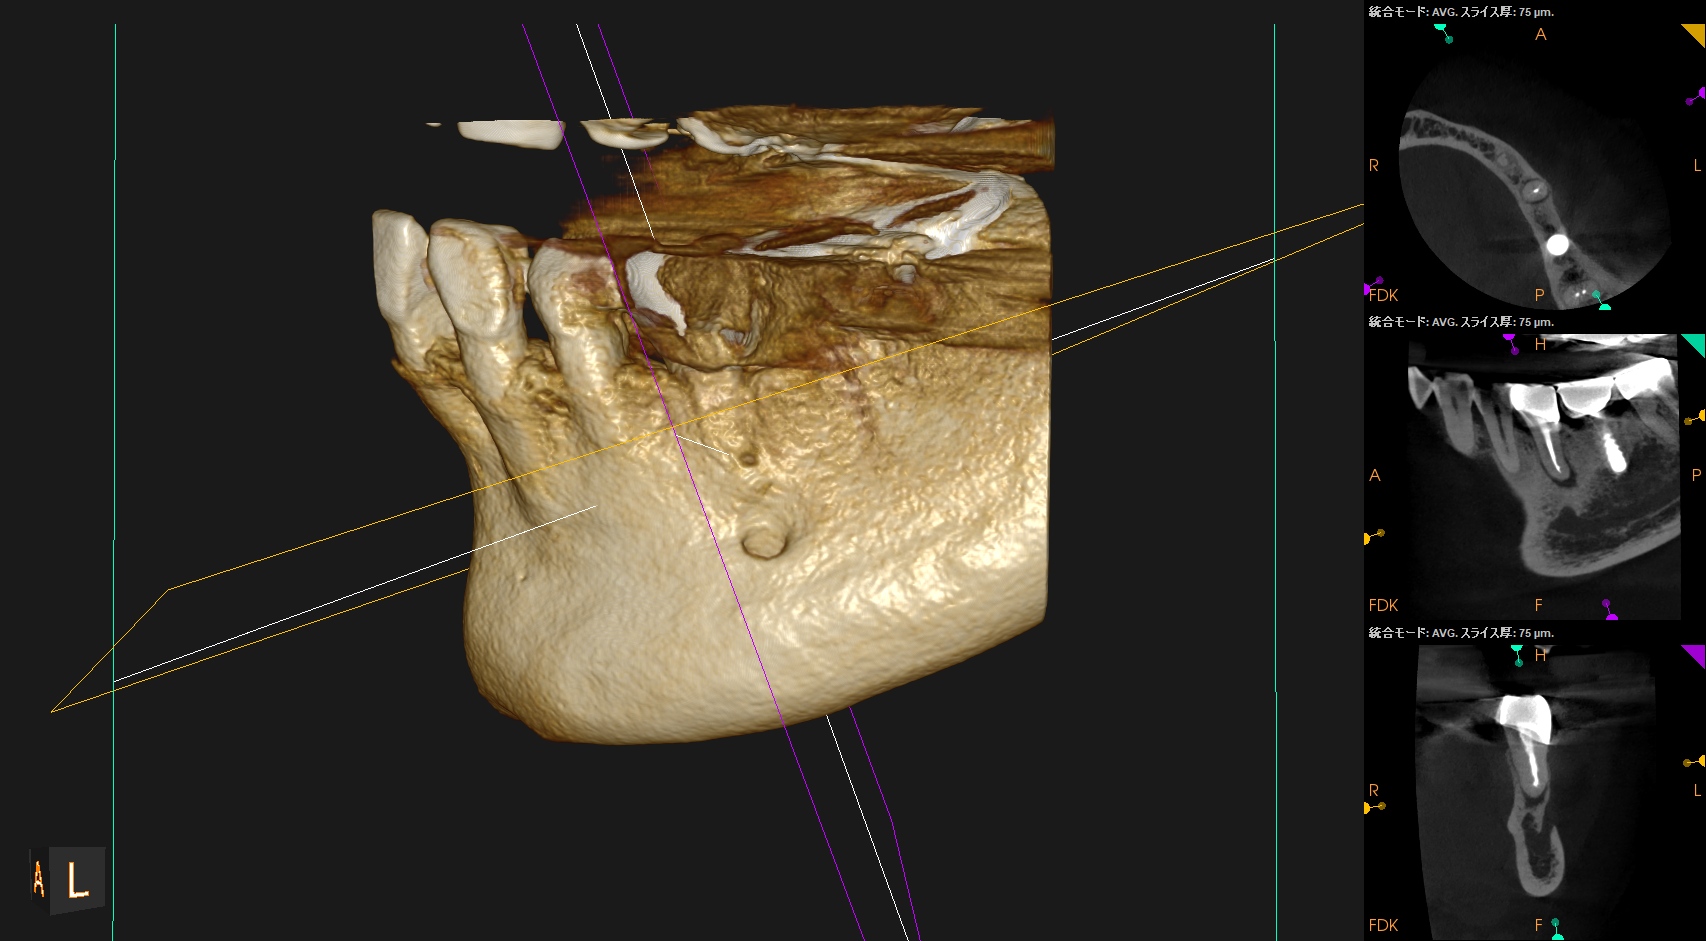

術後のPA, CBCTは以下である。

問題はないだろう。